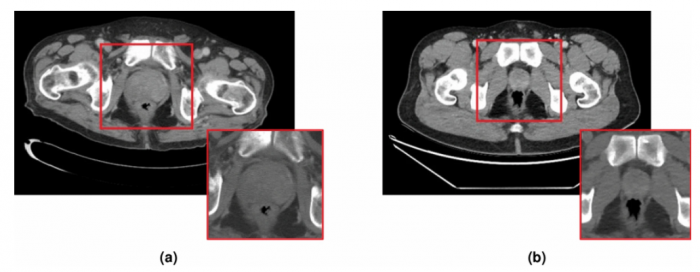

這方面的最新例子來自皇家墨爾本理工大學和圣文森特醫院的研究人員,他們從患有和未患有前列腺癌的無癥狀患者的CT掃描開始。科學家們指出,一般來說,CT掃描對檢測骨骼和關節問題等疾病很有用,但放射科醫生很難用它們來檢測前列腺癌。

利用CT掃描,人工智能軟件被訓練來搜索可能表明該疾病的不規則現象。該工具隨著每次掃描的進行而改進,完善其能力并適應分析不同機器的掃描,最終發現疾病的最小特征。隨著時間的推移,它能夠勝過放射科醫生,在幾秒鐘內檢測出癌癥的生長,甚至在病人出現任何癥狀之前。

“我們已經訓練我們的軟件看到人眼無法看到的東西,目的是通過偶然的檢測發現前列腺癌,”研究報告的作者、皇家墨爾本理工大學的Ruwan Tennakoon博士說。“這就像訓練一只嗅覺靈敏的狗--我們可以教人工智能看到我們自己的眼睛看不到的東西,就像狗可以聞到人類鼻子聞不到的東西一樣。”